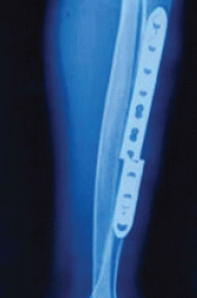

Functional Outcomes and Surgical Utility of the Modified Schatzker Four-column Concept in Proximal Tibial Plateau Fractures: A Prospective Observational Study

Sreekanth Kashayi-Chowdojirao , K K Kiran Kumar , Pankaj Kabra , K Joy , Safia Sultana

………………………………p.290-297